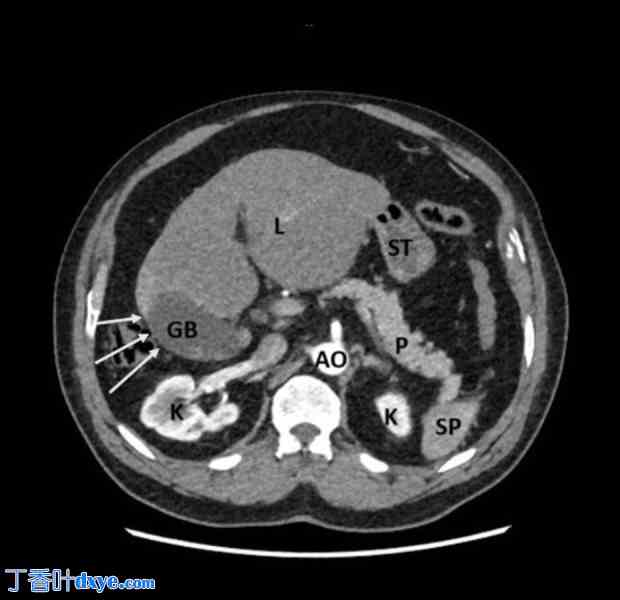

为排除任何异常,患者进行了腹部静脉造影CT检查。CT显示胆囊位于肝脏右背侧,胆囊颈部嵌顿有结石(图1)。肝右叶严重发育不全,左叶代偿性肥大。动脉视图可见肝右动脉起源于肝门,向下延伸,末端闭锁,可能通向萎缩的肝右叶(图2)。静脉视图可见肝右静脉(图3)。

图 3.

增强 CT,静脉期。(A) 门静脉主干 (MPV); (B)左门静脉 (LPV) 和右门静脉 (RPV)。